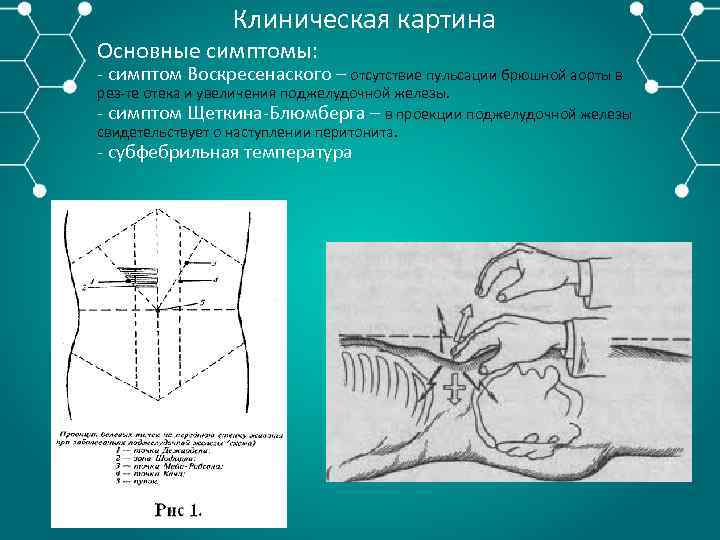

Клиническая картина Основные симптомы: симптом Воскресенаского – отсутствие пульсации брюшной аорты в рез те отека и увеличения поджелудочной железы. симптом Щеткина Блюмберга – в проекции поджелудочной железы свидетельствует о наступлении перитонита. субфебрильная температура